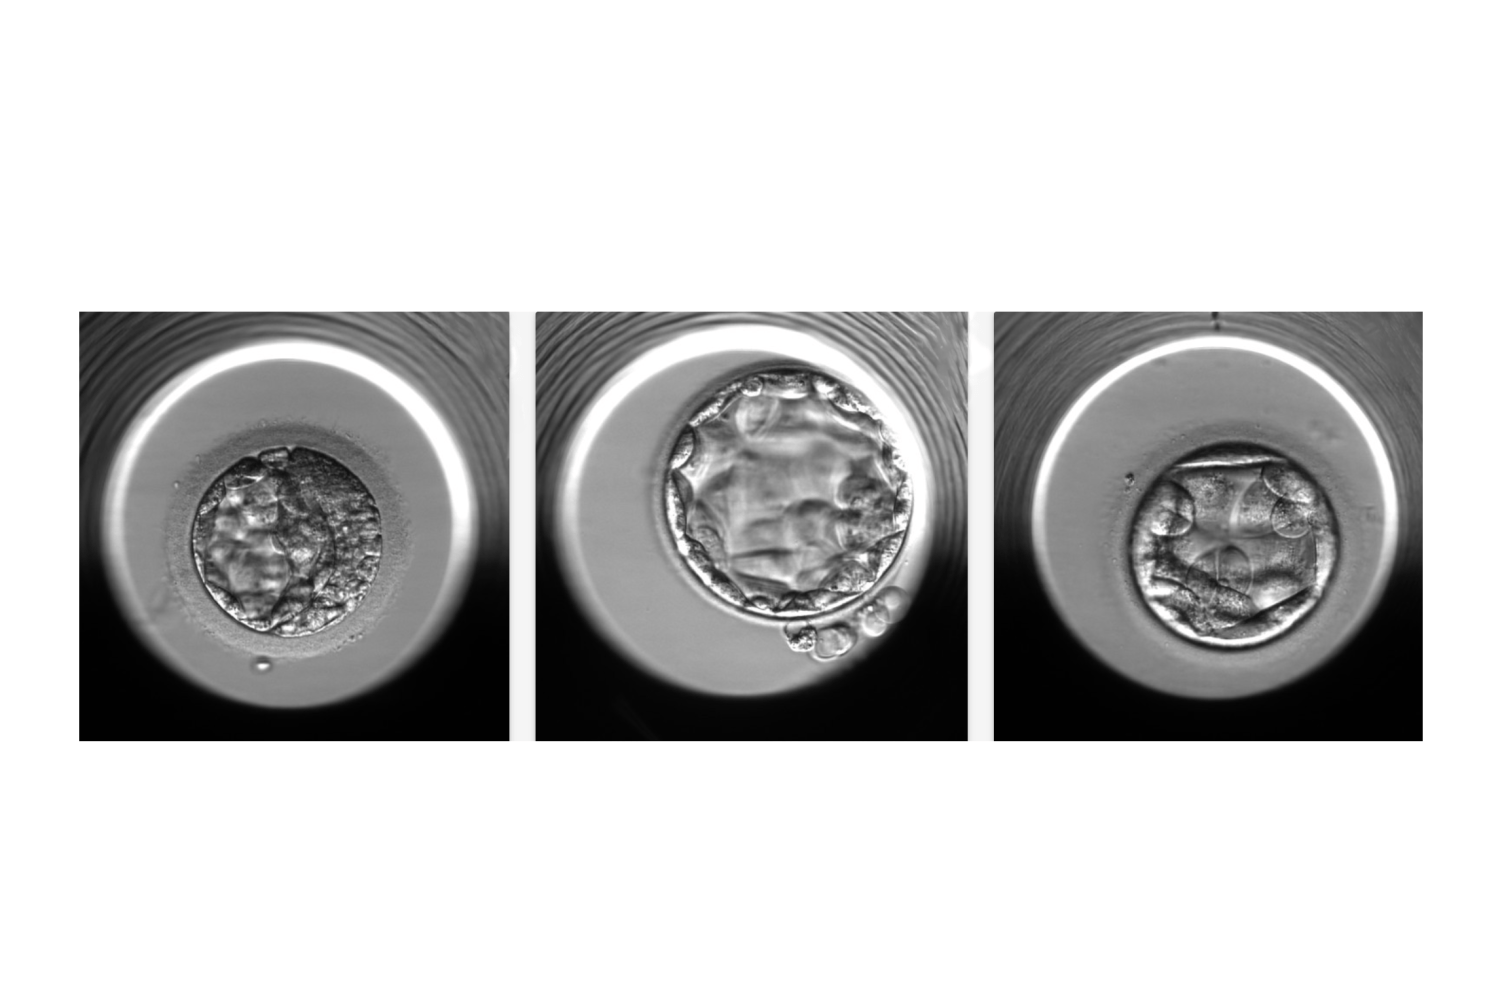

Live Tech News : Human Embryos Grown In Lab For Longer Than Ever Before

www.livetechnews.comhuman embryos lab grown embryo

www.livetechnews.comhuman embryos lab grown embryo

wallpaperaccess.comStages Of Embryo Development

wallpaperaccess.comStages Of Embryo Development